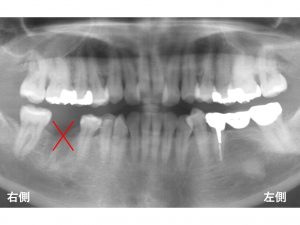

右下の奥歯が欠損している患者様です。

この欠損部をどう治療するか? です。

以下が先日行ったインプラント手術後です。